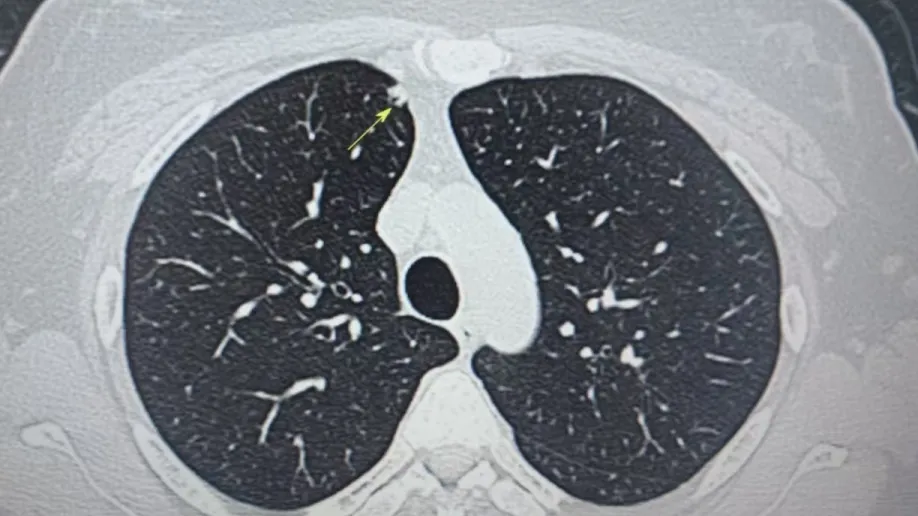

內(nèi)容提要 近年來(lái),肺結(jié)節(jié)檢出率持續(xù)攀升,其發(fā)病群體正呈現(xiàn)明顯年輕化趨勢(shì),更令人警醒的是,有些結(jié)節(jié)雖小,卻暗藏致命風(fēng)險(xiǎn)。葫蘆島市第二人民醫(yī)院肺結(jié)節(jié)診治中心近期接診的35歲劉女士(化名)便是典型一例:她體內(nèi)兩顆直徑僅4mm和6mm的“迷你”結(jié)節(jié),竟被病理證實(shí)為惡性腫瘤!這一案例再次顛覆了公眾對(duì)“結(jié)節(jié)小=安全”的固有認(rèn)知。 專業(yè)研判 為生命贏得轉(zhuǎn)機(jī) 微創(chuàng)精準(zhǔn)切除 四級(jí)手術(shù)顯實(shí)力 小結(jié)節(jié)≠低風(fēng)險(xiǎn) 認(rèn)知誤區(qū)亟需破除 人民醫(yī)院 人民名醫(yī)